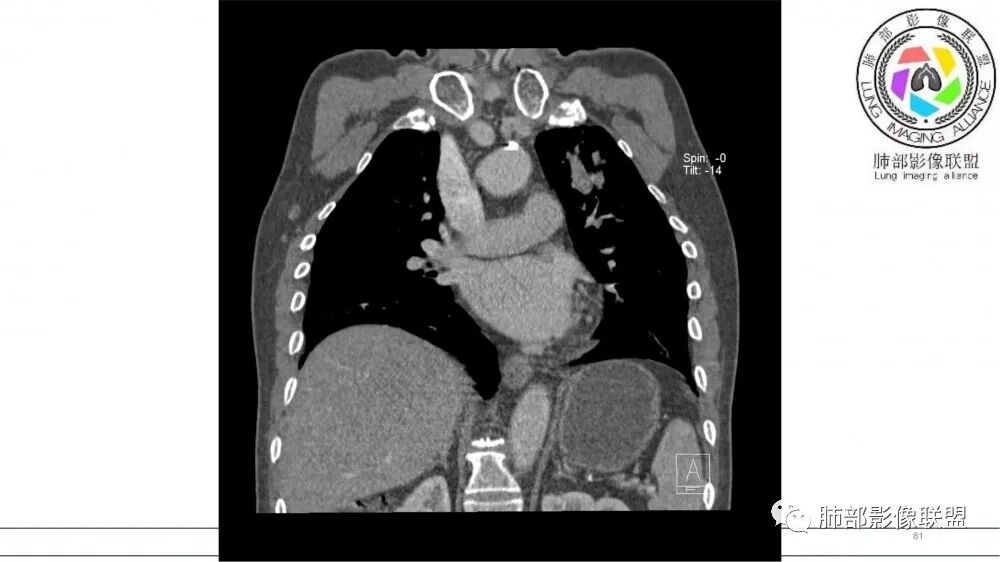

左肺上叶前段支气管内铸形生长软组织影,增强后均匀强化,远侧见斑片状磨玻璃影。考虑恶性病变,粘表?粘液腺?

老年男性,左肺上叶前段支气管内铸形阴影,增强后病灶不均匀强化,内部有坏死?远端可见斑片状阴影(阻塞性肺炎)。考虑恶性病变,老年人,鳞?类癌?粘表不能排除。

左肺上叶前段支气管杵状指样扩张,内见实性组织阻塞性,并强化明显,边缘饱满,周边多发小斑点影,小花小草征,老年男性,长期吸烟史,方向恶性,首选支气管内浸润鳞Ca可能性大。

老年男性,肺气肿,吸烟史,左肺上支气管腔内铸型高密度影,呈指套状,远端多发树芽,增强不均匀强化,考虑鳞癌,鉴别小细胞癌

老年男性,吸烟史,左肺上叶沿支气管塑型生长软组织肿块,轻度强化,周围小花小草,肺门及纵隔淋巴结增大,倾向恶性病变,鳞癌?粘表?

老年男性,吸烟史,左肺上叶支气管铸形,变窄,轻度强化,周围阻塞性炎症,左肺门肿大淋巴结,考虑恶性,小细胞鉴别鳞癌

老年吸烟男,左肺上叶支气管堵塞,远端小花小草,纵隔未见肿大淋巴结,考虑鳞癌,建议进一步支气管镜检查

左肺上叶尖后段支气管近端截断,远端见高密度铸型,远侧见阻塞性改变,老年男性,吸烟史,考虑恶性,鳞癌。ABPA代排

老年男性,长期吸烟史。左上肺前段沿支气管走形的指套样病变,增强可见病灶强化(排除结核、ABPA(也无气喘症状)),远端多发点状高密度影。考虑恶性肿瘤,鳞癌可能性大。

有强化吧,淋巴结大

指套征,扩张支气管内软组织强化,远侧肺野阻塞性炎,纵隔、左肺门肿大淋巴结;老年男性,吸烟,考虑鳞癌,鉴别小

老年男性,术前检查肺气肿背景,左肺上叶结节,沿支气管蠕虫样生长,左肺门及纵隔淋巴结肿大,增强扫描不均匀强化,血管包绕,结合吸烟史,考虑小细胞肺癌。

2021年8月6日晨读病例结果:小细胞肺癌

指套征:是影像征象,胸部平片表现为手指状密度增高影,以肺门为中心呈放射状分布,CT显示扩张支气管内低密度黏液栓形成或实性病变,呈管状、树枝状或卵圆形密度增高影;支气管扩张伴近端梗阻时,扩张支气管内部黏液分泌物不能排出而形成。可以伴随远端空气潴留征、阻塞性炎症。

研究报道,中心型 SCLC 经 CT 扫描后通常支气管表现为鼠尾样狭窄,肺门或纵隔肿块明显,由于肿块沿管壁生长表现为顺延支气管形态的不规则形状。病灶相对特征性影像学表现比如鸭蹼状、腊肠状、葫芦状及葡萄状改变,可以出现血管包埋,很少有空洞、空泡,较少引发肺不张,阻塞性炎症成都较轻。与一般肺癌比较,恶性程度高,侵袭力强、病灶很小就容易远处转移!Herzberg 等[19]研究指出,20%以上 SCLC 倍增时间短,预后不良。